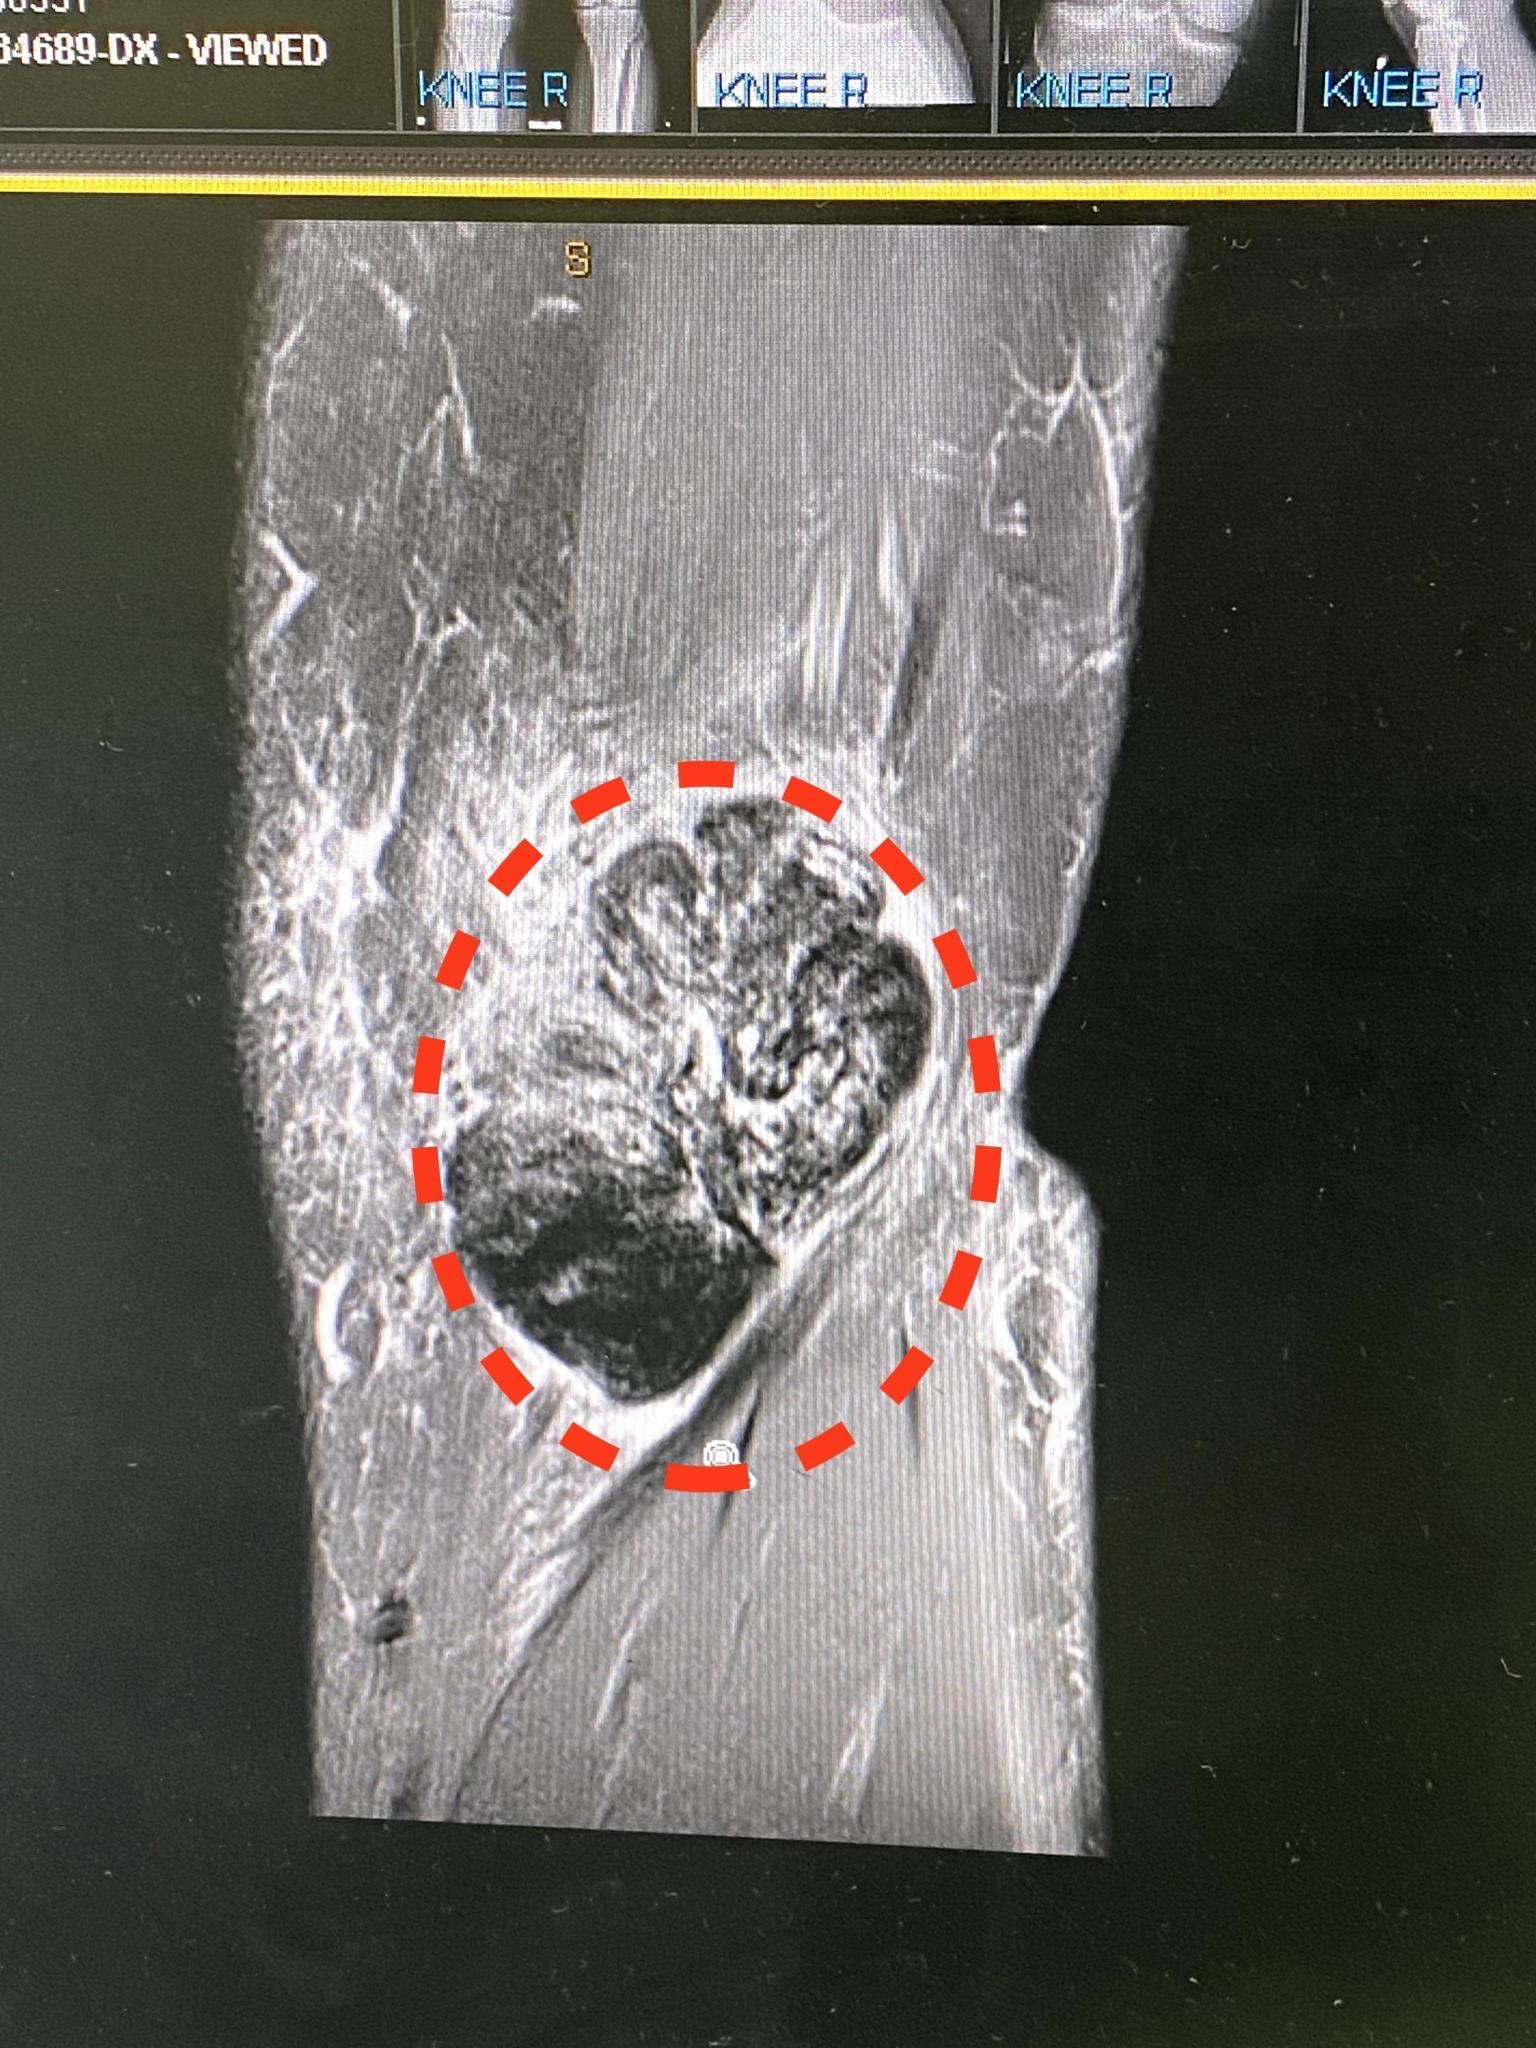

So many questions and so few answers, but when you hear the word Tumour your mind plays tricks and it is then very hard to completely take everything else in terms of what is being said, the next keywords were – “I will be referring you to the Tumour Clinic at Flinders Cancer Clinic” for further care/treatment. Hey, this is not my first rodeo, can we have a quick chat about options, I was not looking for a clinical plan in terms of treatment. I wanted to understand deeper what it was and from an orthopedic viewpoint only how this would be tackled. Surgically remove the tumour on the inside of the knee, arthroscopically repair the tear but the concern was the tumour is basically right in the middle of the knee joint between the Femur and the Tibia, there was further chat about whether the tumour is attached to the bone or not.

Today (04/04) was the answer day, let’s not beat around the bush… the diagnosis was better than we had planned for 100%, it is a rare disorder called Pigmented Villonodular Synovitis (PVNS), it is thought to affect 2 people in every 1 million. While the initial diagnosis was a huge win and relief, this disorder comes with its own sets of challenges, the particular tumour name is Giant Cell Tumour.

GCT – is a rare, aggressive non-cancerous tumour.

Back to my story, we have been advised that while I have 2 well-formed tumours (as below), there are approx 2-3 pebbles within and around the joint to consider as well, these must be removed. If untreated the risk is the tumour keeps growing, but will bleed, this will then have further impacts and will attack the bone and cartilage causing more damage.